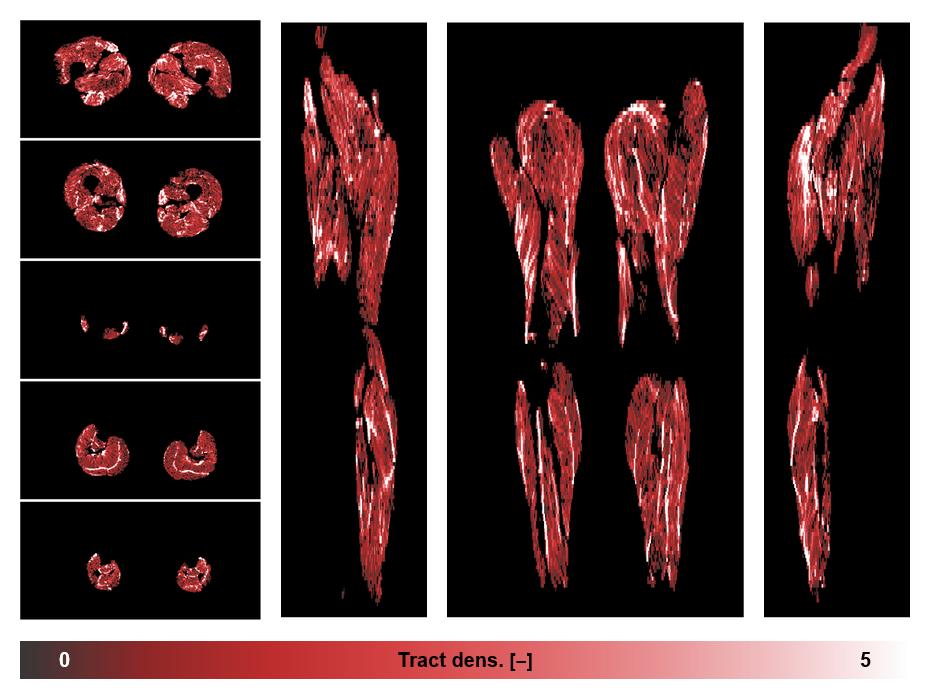

• Muscle fiber density map

Muscle fiber tract density map based on whole leg DTI based fiber tractography.